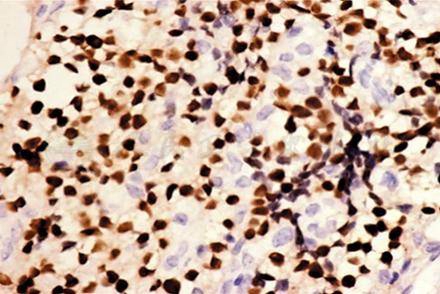

大多数多发性骨髓瘤病例要通过眶内肿瘤标本的组织病理、免疫组化染色检查确诊,CD45(部分+)、CD43 (+++)、CD68/KPI(+)(图2)、Mum-1(+)(图3)、KI-67阳性率70%证实诊断,(CD43 慢淋B细胞、T细胞,CD68/KPI 髓细胞、巨噬细胞,CD45淋巴细胞、髓细胞、Mum-1浆细胞分化抗原)。

图3 瘤细胞Mum-1表达阳性 IHC×400